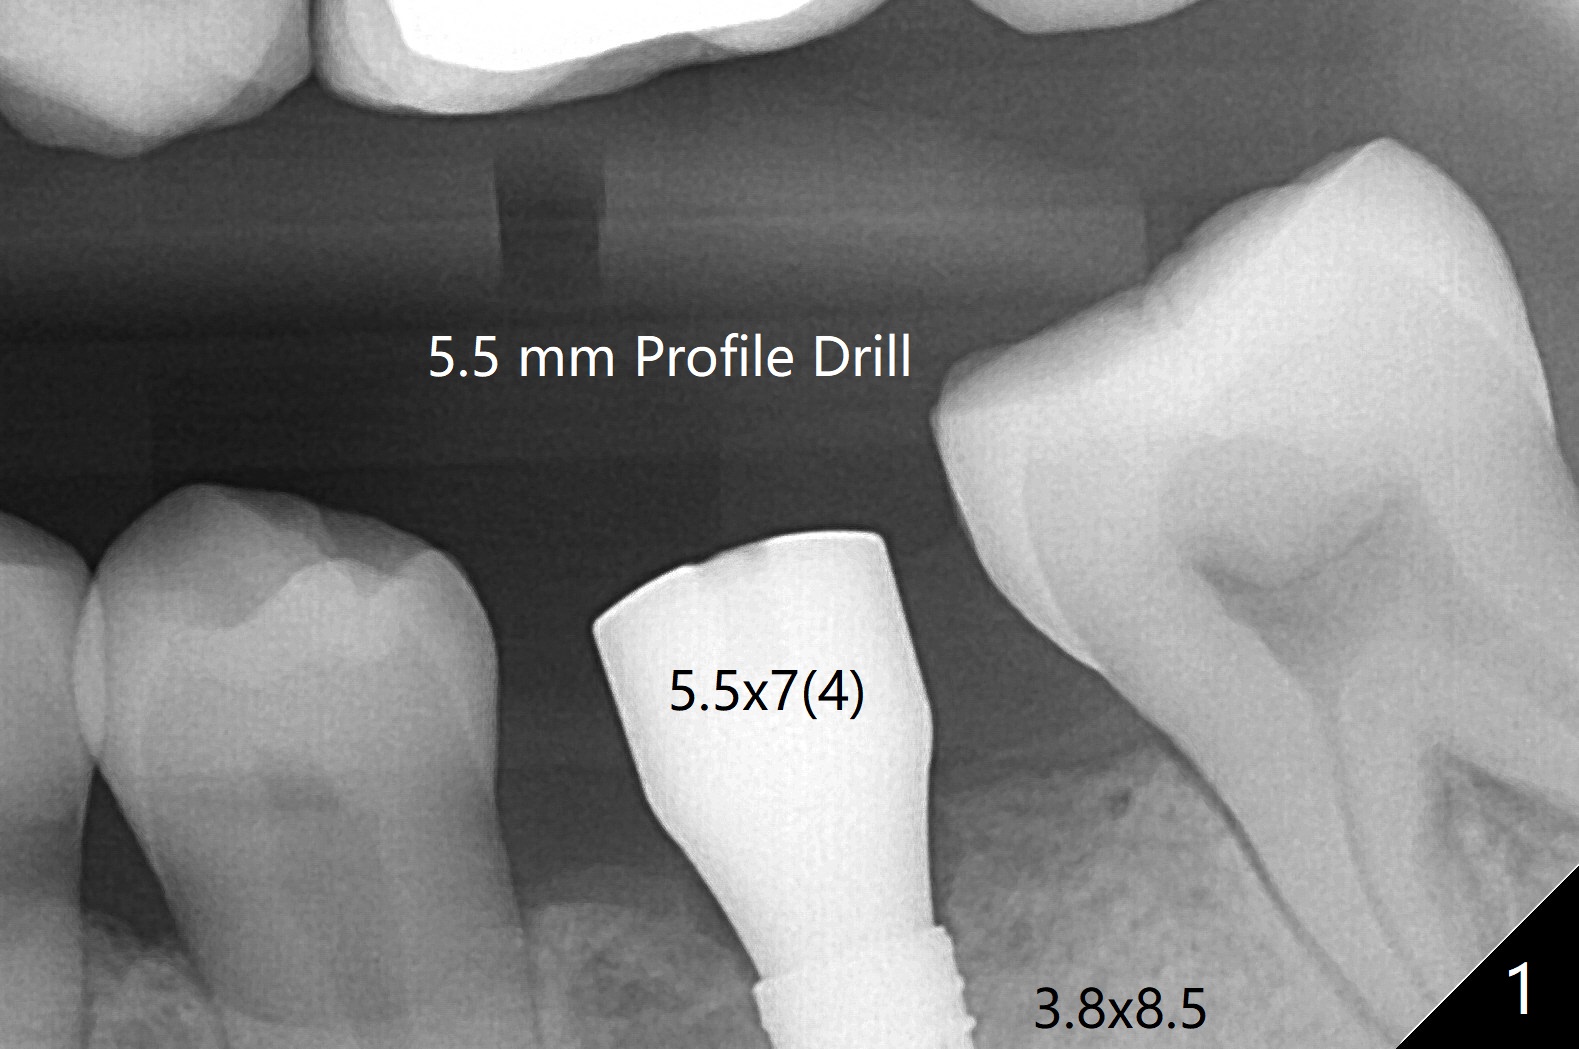

尽管有骨质疏松症,必须使用4.0毫米功螺纹后才能植入3.8x8.5毫米植体。牙周探针检查证实植体近中,远中牙槽嵴下。使用5.5毫米Profile钻头,放置5.5x7(4) 毫米愈合基台,后者好像完全就位(图一,二)。